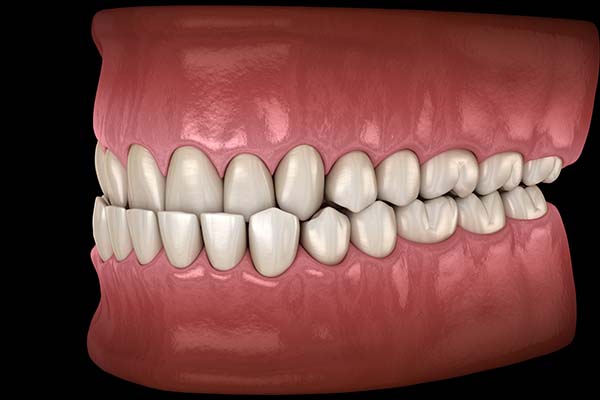

An orthodontist will address many challenges that patients have. Underbites are among the most frequent complaints that people bring to orthodontic offices. This condition occurs when a person’s lower teeth extend farther than the upper teeth. Some underbites are minor and barely noticeable. Others, though, make the jaw protrude outwardly so much that it can make the person feel self-conscious.